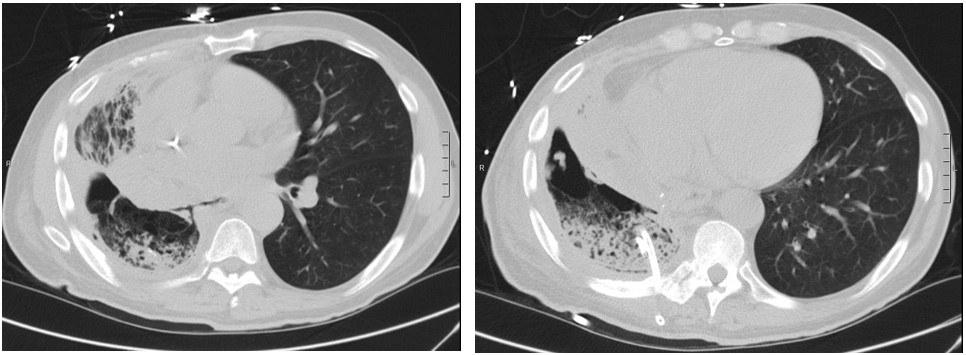

On evaluation, he was tachycardic with fever (38.6 °C) and exhibited decreased air entry to his RLL. Contrast enhanced Computed Tomography (CT) of the chest was done and showed right middle and lower lobe consolidation with areas of cavitation and a moderate right sided pleural effusion (Image 1). The patient was started on broad spectrum antibiotics. A repeat CT chest was obtained on day 7 due to clinical deterioration, which showed a new right-sided hydropneumothorax (Image 2). A pigtail chest tube was placed by Interventional Radiology that drained brown, markedly turbid fluid that was exudative based on Light’s criteria (pH < 6.3, LDH 575). His chest tube output continued to drain copious volume (average: 400 ml/day) of turbid, foul-smelling fluid with particulate matter over the next few days. Microbiological data identified polymicrobial growth of oral/upper respiratory tract: GPC in pairs and chains, GPRs, and candida glabrata. Subsequent CT chest after chest tube placement is shown below (Image 3):